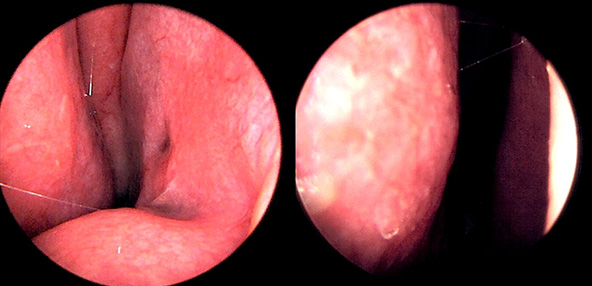

본 사진은 의료기관에서 진료를 본 환자이고, 전후 사진 인물이 동일인이며,동일조건에서 촬영이 되었습니다.